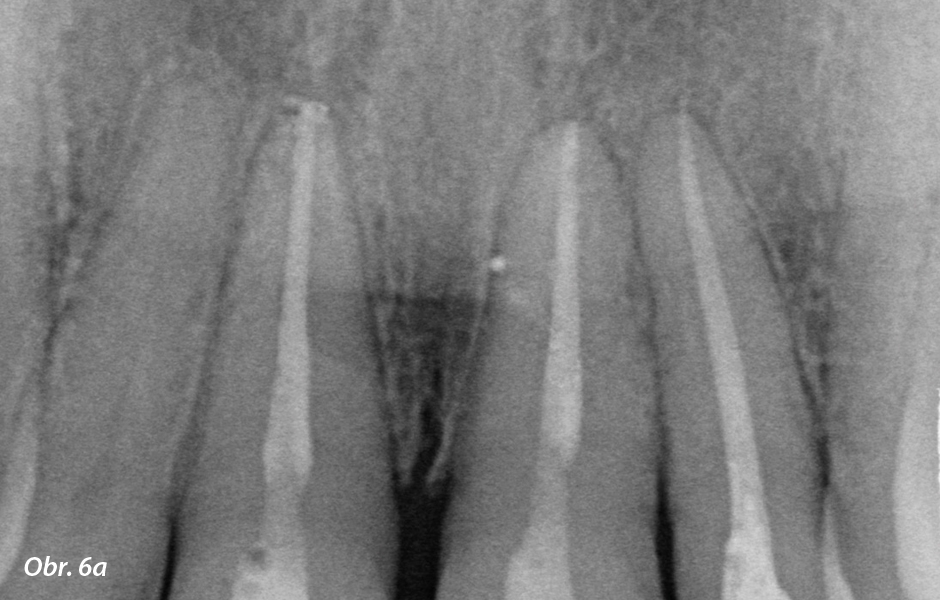

První případ Dr. Matthes byla estetická korekce předních zubů před protetickým ošetřením. Stomatoložka uvádí: „62letá pacientka si přála ošetření horních řezáků 12, 11, 21 a 22 keramickými korunkami. Zuby byly endodonticky ošetřeny alio loco po traumatu předních zubů při nehodě na kole asi před 1,5 rokem a doplněny kompozitem, který se již částečně odštípl.

Klinický nález odhalil kompresi v maxile i mandibule, zub 21 inklinovaný vestibulárně a intruzi dolního frontálního úseku. Počáteční protetická situace nebyla optimální. Pro dosažení co nejlepšího estetického výsledku a vzhledem k tomu, že jde o náročnou pacientku, jsem doporučila ortodontickou předprotetickou léčbu transparentními alignery pro vytvoření dostatečného prostoru pro preparaci a umístění korunky. Pacientka souhlasila s ortodontickou léčbou, která byla odhadnuta na šest měsíců. V srpnu 2019 byly pořízeny RTG snímky a fotografie situace (zepředu, z profilu a horní i dolní čelisti při pohledu z okluze). Navíc byly provedeny situační skeny horní a dolní čelisti pomocí intraorálního skeneru 3Shape TRIOS.“

Klinická výchozí situace. Endodonticky ošetřené zuby 11–22 po úrazu. Proteticky mají být ošetřeny zuby 12–22 (zdroj: zubní lékařka Swantje Matthes).

Kontrolní snímky předních zubů horní a dolní čelisti před preparací (zdroj: zubní lékařka Swantje Matthes).